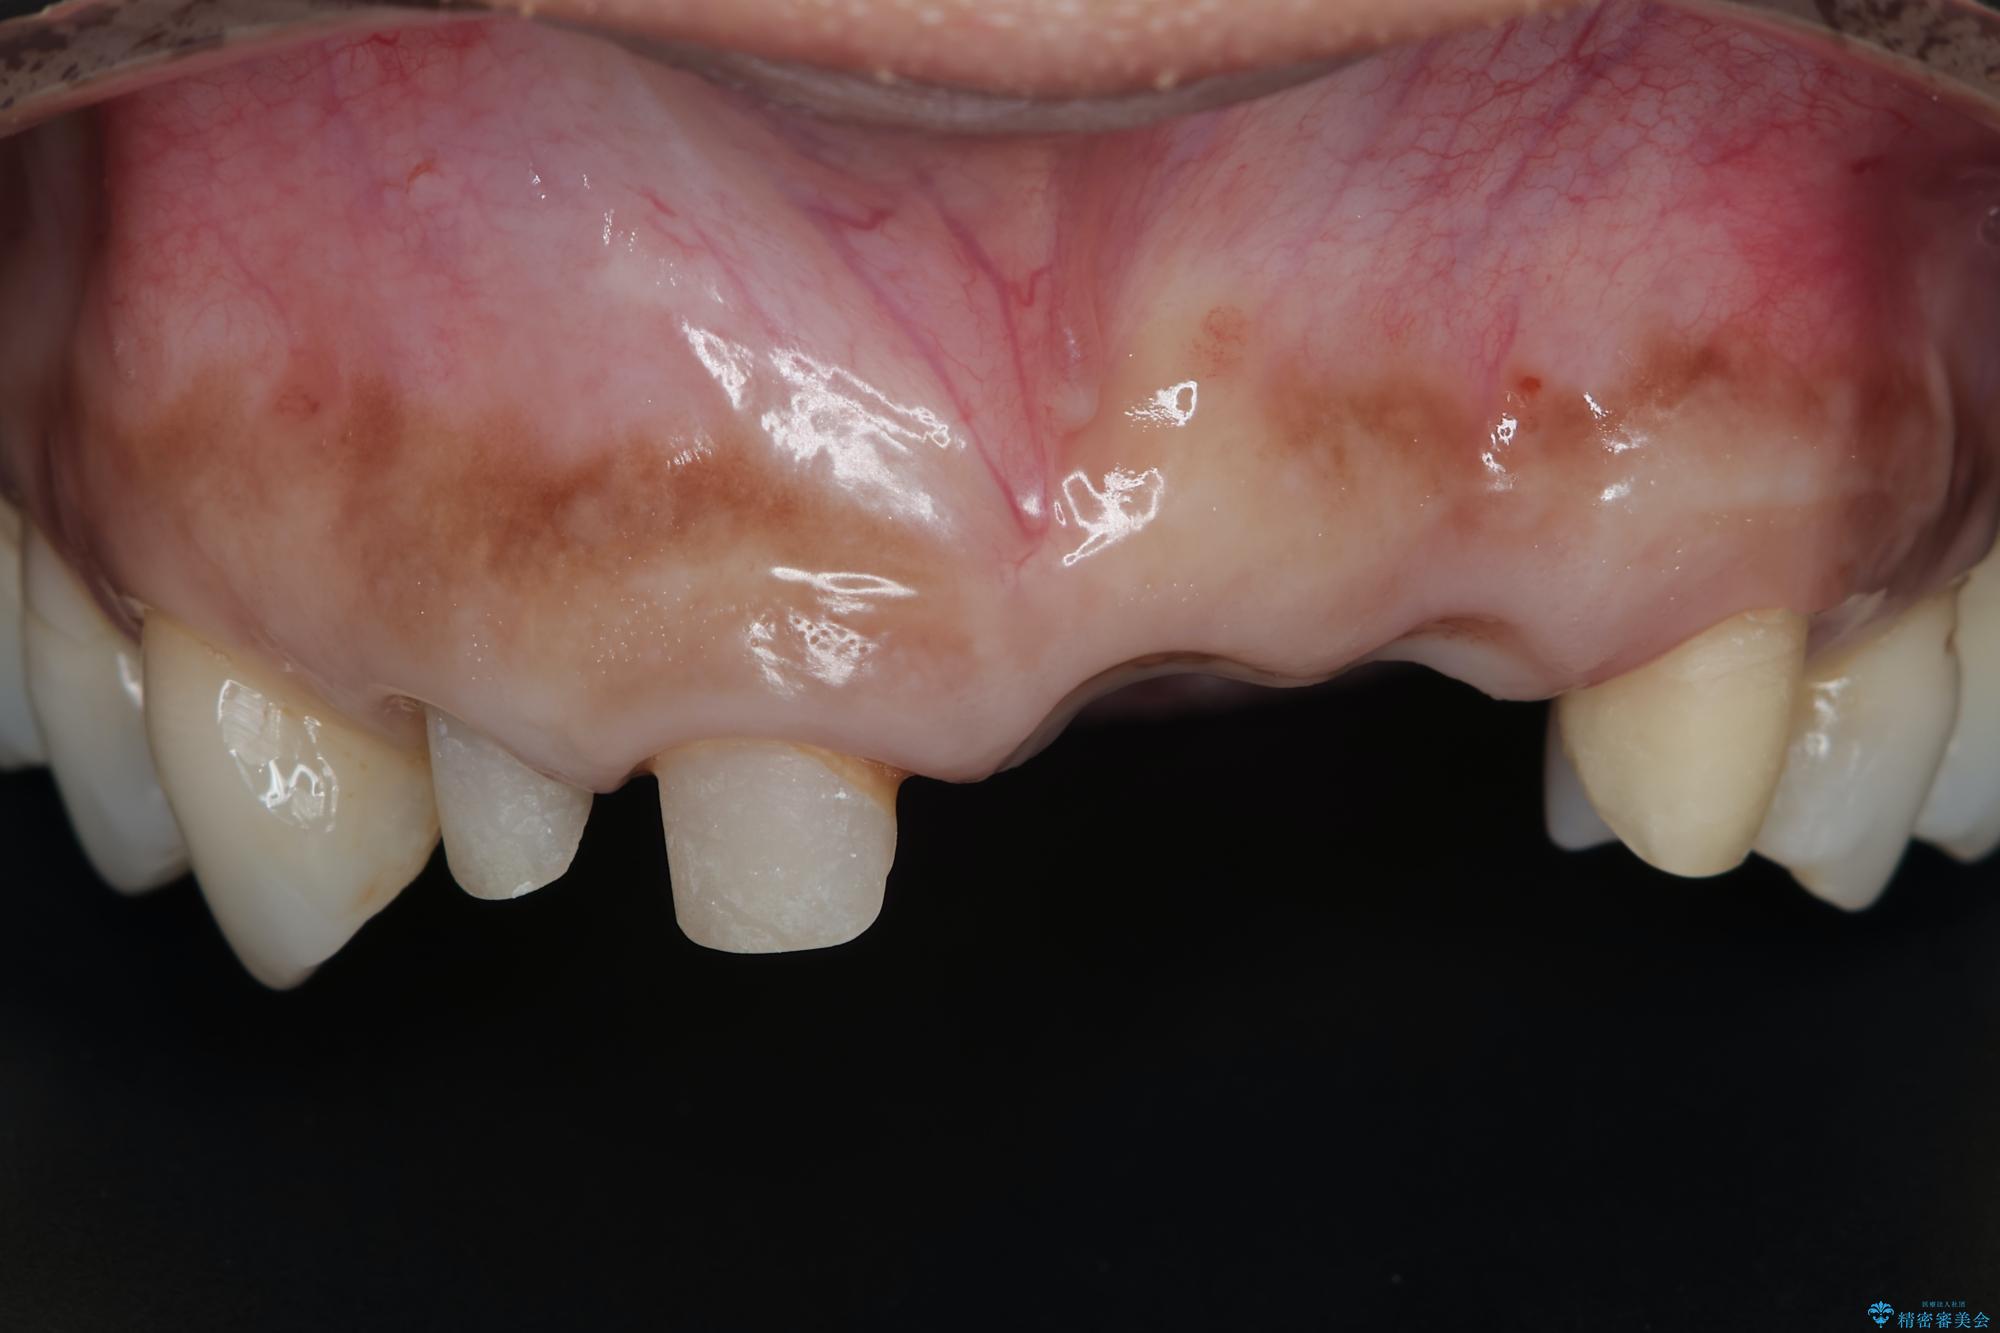

抜歯時に可及的に歯肉のボリュームを保つよう骨充填材とコラーゲン製剤による填塞を行い審美的かつ機能的なブリッジとなるよう治療を進めます。

治療中

歯槽堤保存術を併用したブリッジ治療 治療中画像 歯槽堤保存術を併用したブリッジ治療 治療中画像 歯槽堤保存術を併用したブリッジ治療 治療中画像 歯槽堤保存術を併用したブリッジ治療 治療中画像 歯槽堤保存術を併用したブリッジ治療 治療中画像 歯槽堤保存術を併用したブリッジ治療 治療中画像 歯槽堤保存術を併用したブリッジ治療 治療中画像